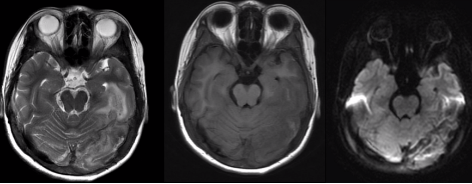

2.脑出血影像学表现

信号特征复杂,与血管内红细胞的完整性及血红蛋白的演变有关。

(1)超急性期 CT 高密度;T1WI 呈等或略低信号,T2WI 呈高信号。

(2)急性期 CT 高密度;T1WI 呈等信号,T2WI 呈低信号。

(3)亚急性期 CT 密度逐渐减低与脑实质相仿 1w、t2 呈高信号。

(4)慢性期 CT 囊性病灶,可见钙化;T2WI 高信号血肿周围被低信号含铁血黄素包饶。